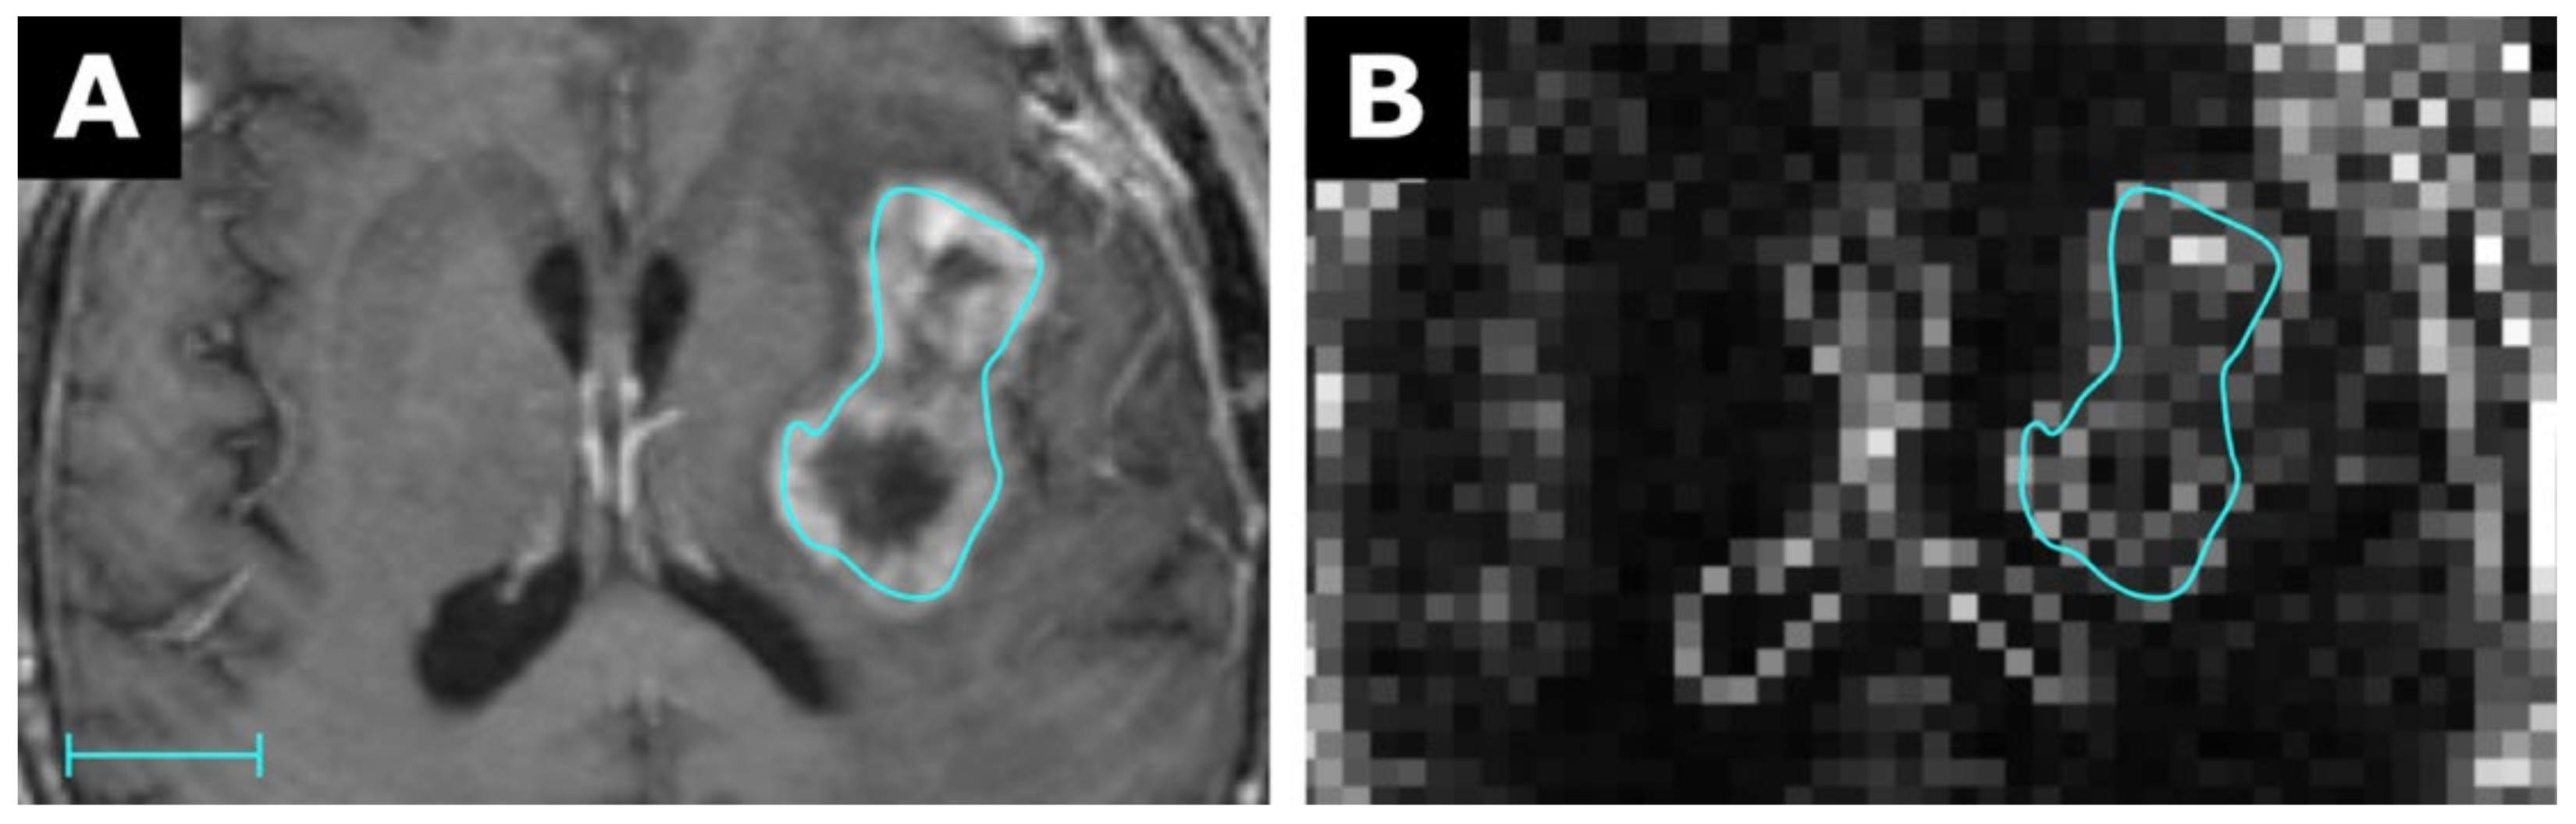

3.1. Proof of Concept Examples